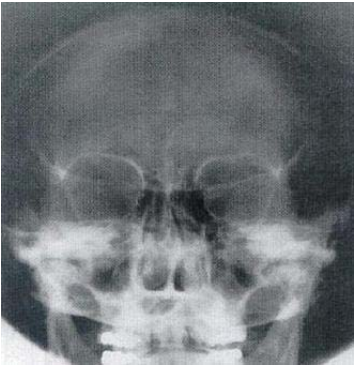

4.此影像的照射方法為何?

(A)SMV(submentovertex)projection (B)Towne method (C)Caldwell method (D)Waters view